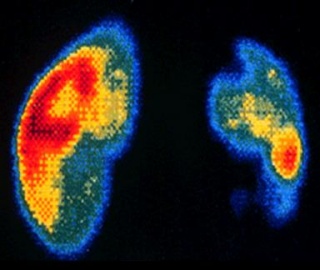

Сцинтиграфия почек показывает нормальную функцию почек в зависимости от возраста пациента и состояния его здоровья, а также относительную позицию, размер, конфигурацию и локализацию почек. Первичные изображения кровотока отражают кровообращение в обеих почках. Пациентам, у которых по данным сцинтиграфии почек предполагают повреждение или обструкцию, для получения дополнительной информации требуются другие методы диагностики, такие как КТ (компьютерная томография) или ультразвук. Кроме того, если почки неправильного размера, имеют необычный контур или необычно расположены, могут требоваться другие методы визуализации.

Это радионуклидное исследование почек, дающее возможность изучить состояние почечного кровотока с помощью радиофармпрепарата 99 mТс-ДТПА.

Ангионефросцинтиграфия дает изображение распределения данного препарата в паренхиме почек и графическую регистрацию трансфера препарата в почках. Полученная информация позволяет оценить почечный кровоток в целом, в каждой почке и отдельных ее частях. Метод исследования имеет большое диагностическое значение в выявлении нарушений почечного кровоснабжения в каждой почке отдельно, что позволяет оценить наличие стеноза почечной артерии и дифференциальной диагностике кист и опухолей.

Сцинтиграфия почек проводится при различных заболеваниях мочевыводящей системы. Исследование выполняется для оценки формы, размеров, положения почек, локализации и степени выраженности патологического процесса, а также оценки функционального состояния паренхимы почек.

Сцинтиграфия почек представляет собой диагностическую процедуру, которая применяется для обнаружения различных заболеваний мочевыводящей системы на ранних стадиях их появления. В процессе исследования в организм пациента вводится радиофармпрепарат, а затем его движение через почки отслеживается специальным оборудованием.